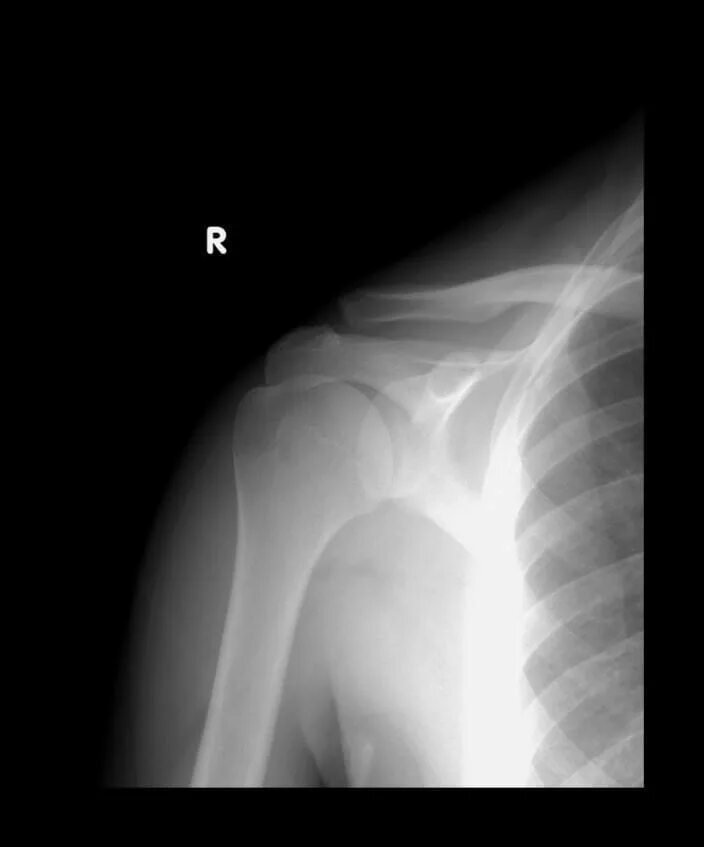

Дегенеративные изменения акромиально ключичного сустава